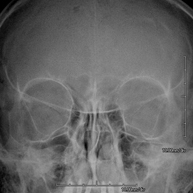

- RX Cráneo

Técnica mediante la cual, utilizando rayos X, se obtienen imágenes del cráneo para su estudio. Indicaciones: traumatismo, cierre precoz de suturas craneales. - RX Senos Paranasales

- Paranasal Sinuses X-ray

This technique uses X-ray rendered imaging for examining the paranasal sinuses. Indicated for: headache, chronic cough.